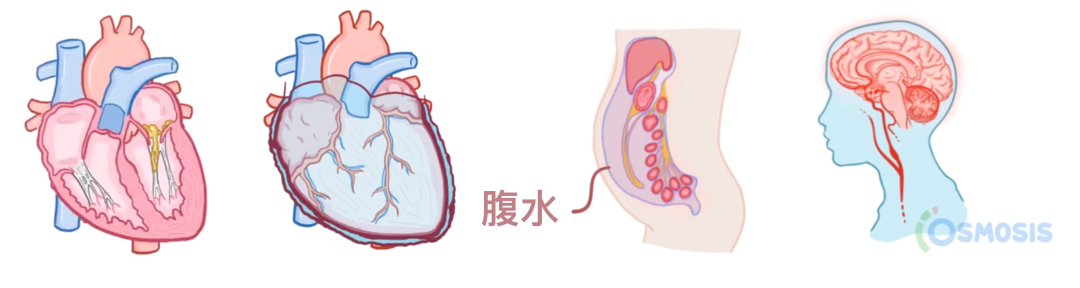

一旦进入血流,肺炎链球菌还可以引起肺炎链球菌性心内膜炎,形成称为赘生物的菌块,从而损伤心脏瓣膜。

它也可能感染心包,引起化脓性心包炎,即脓液在心包腔内聚集。

最后,肺炎链球菌也可以经血流扩散至腹膜,引起自发性细菌性腹膜炎。

这种情况在发生肝硬化并出现腹水的患者中更为常见,也就是腹膜腔内液体过多。